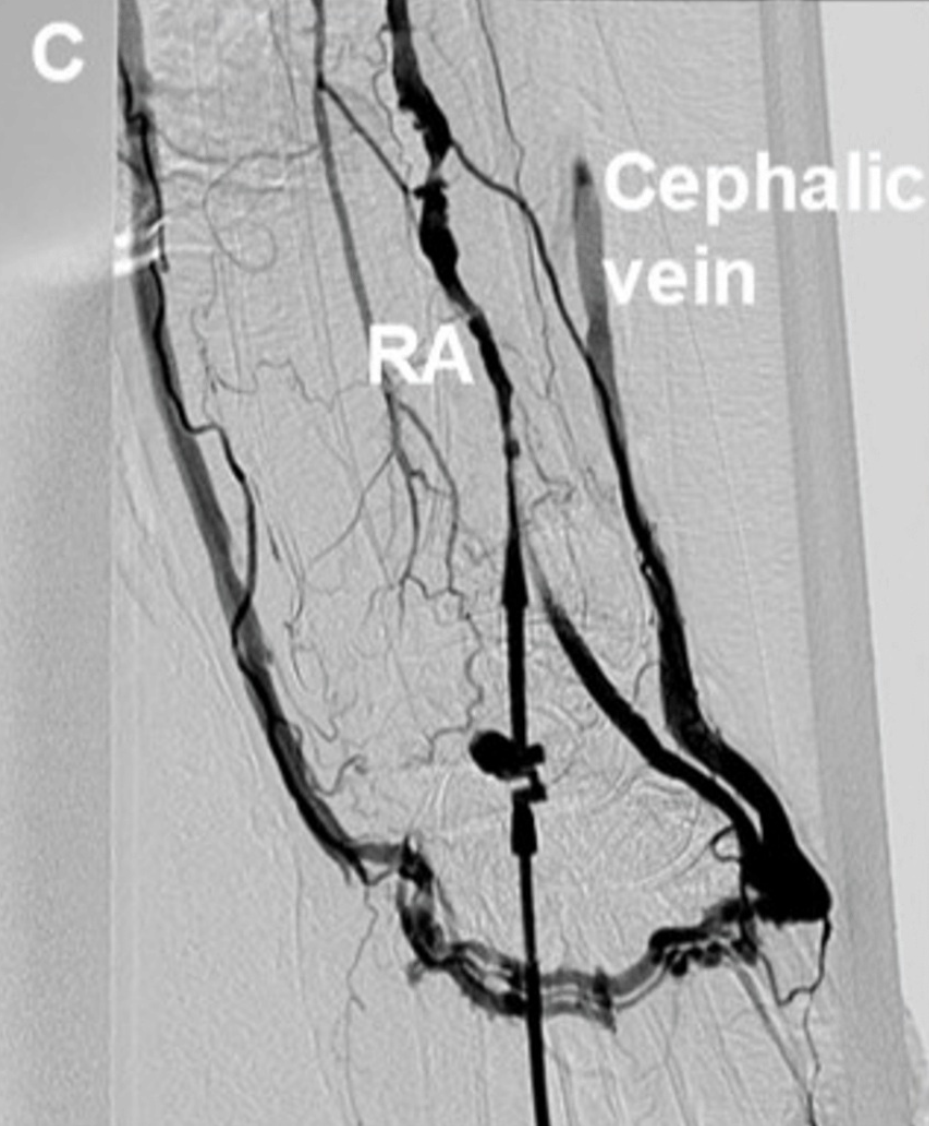

图1.dTRA形成动静脉瘘的照片、超声表现和血管造影图像。

(A)观察到扩张的头静脉。(B)箭头显示动静脉瘘的入口,即桡动脉与静脉连接处。浅表超声检查发现远端桡动脉有一个直径为2.0mm、流速为3.75m/s的动静脉瘘。(C)桡动脉造影。显示远端桡动脉与手背静脉网之间存在分流,并且头静脉和贵要静脉显影。分流位于桡动脉至靠近拇指掌骨的静脉处。(D)常见的远端桡动脉穿刺部位(三角形)和本例的穿刺部位(星形)。

通过穿刺常规左侧桡动脉进行了心导管检查。插入21G套管,在植入鞘管前,向左桡动脉注射造影剂。结果显示远端桡动脉与手背静脉网之间存在分流,并且头静脉和贵要静脉显影(图1C,视频2)。

显示远端桡动脉与手背静脉网之间存在分流,并且头静脉和贵要静脉显影。分流位于桡动脉至靠近拇指掌骨的静脉处。